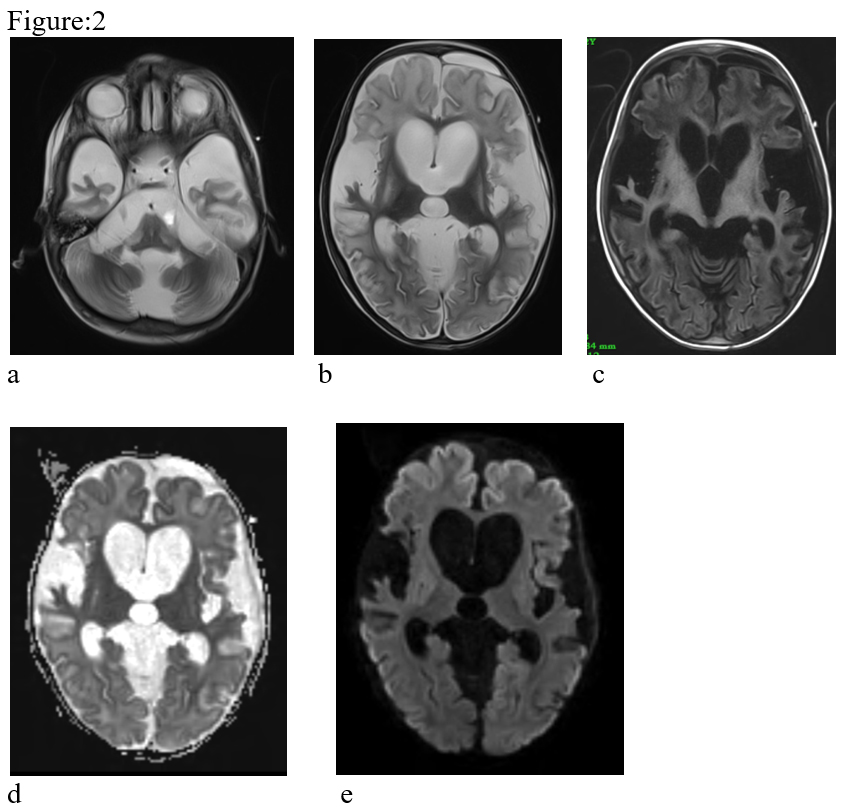

Figure:1- T2 hyperintense & T1 hypointense symmetrical lesions in bilateral basal ganglia regions & widening of the sylvian fissures bilaterally (a, b & c). The basal ganglia lesions reveal restricted diffusion on DW images (d & e). Subdural haematoma (acute to chronic) is seen in bilateral fronto-temporal & left parietal regions (f).

Magnetic resonance imaging of the brain is the modality of choice to investigate children with possible GA-1. MRI shows bilateral symmetrical basal ganglia T2 & FLAIR hyperintensity which appear hypointense on T1 weighted images. T2 & FLAIR hyperintense lesions are also noted in substantia nigra, dentate nucleus. Symmetrical T2 white matter hyperintensities are also observed in periventricular & subcortical regions. The lesions in the acute stage show diffusion restriction with progressive atrophy in the chronic stage. No demonstrable susceptibility change or contrast enhancement is seen in the lesions. MR spectroscopy shows presence of lactate peak in acute lesions. Common presentations include enlarged extraaxial CSF spaces predominantly in the anterior temporal regions, wide sylvian fissures & ventricular enlargement. Wide sylvian fissures reveal typical Batwing appearance2. There may be subdural haematoma possibly due to stretching of bridging veins in the enlarged extraaxial fluid space3. Enlargement of optic chiasm with signal alteration in the anterior intracranial visual pathway has also been reported rarely4.